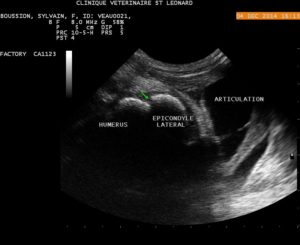

Il a ensuite réalisé un bloc échoguidé du plexus brachial, en utilisant une sonde sectorielle micoconvexe et une aiguille spinale.

Le positionnement de la sonde dans le creux axillaire et l’introduction de l’aiguille dans une direction cranio-caudale sont montrés ici :

Avant injection, les flèches vertes montrent les nerfs du plexus brachial, sous le muscle pectoral, en coupe transversal.